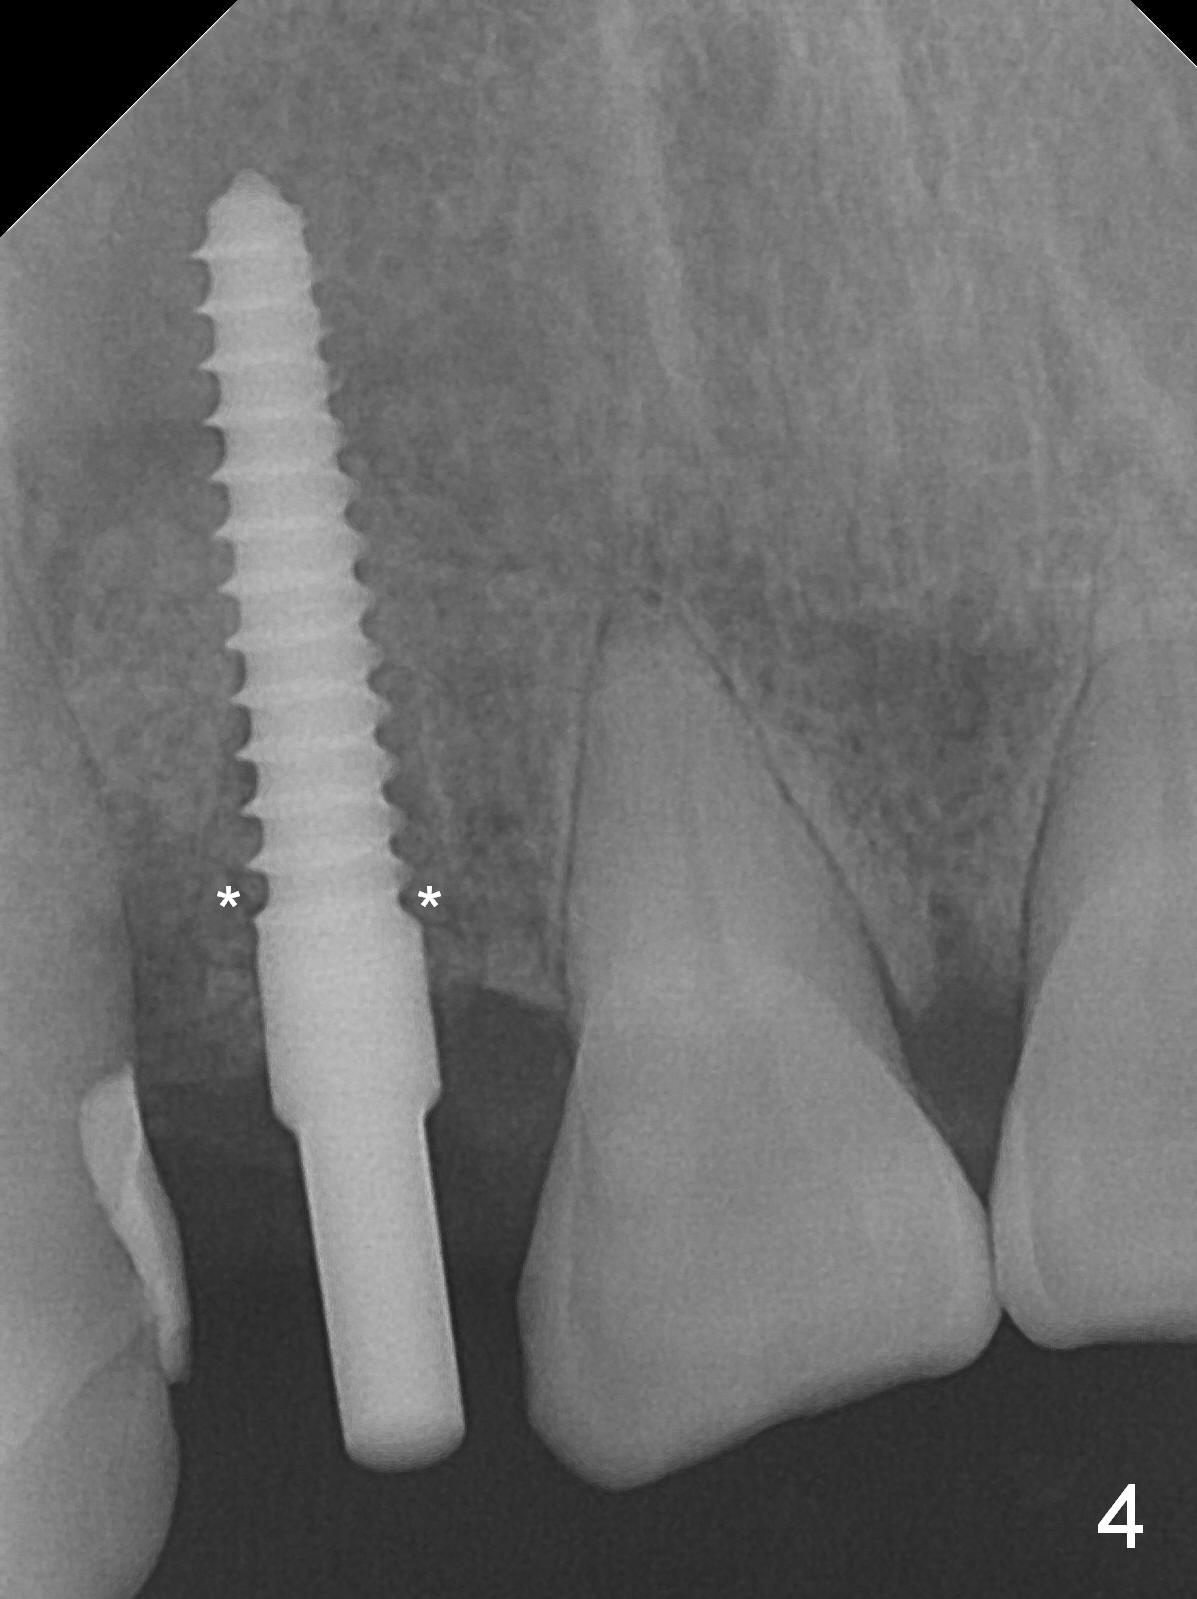

When the flaps are raised, the buccal plate is found to be perforated (Fig.2 *); osteotomy is being established in the narrow palatal wall (<). When a 3x17 mm (tissue-level) 15 ° 1-piece implant is placed (Fig.3,5 P), the incisal end of the implant is between the incisal edge of the central incisors and that of the tooth #10 (Fig.6) so that the temporary crown (Fig.7 T) is slightly buccal with sufficient palatal clearance with the opposing dentition.